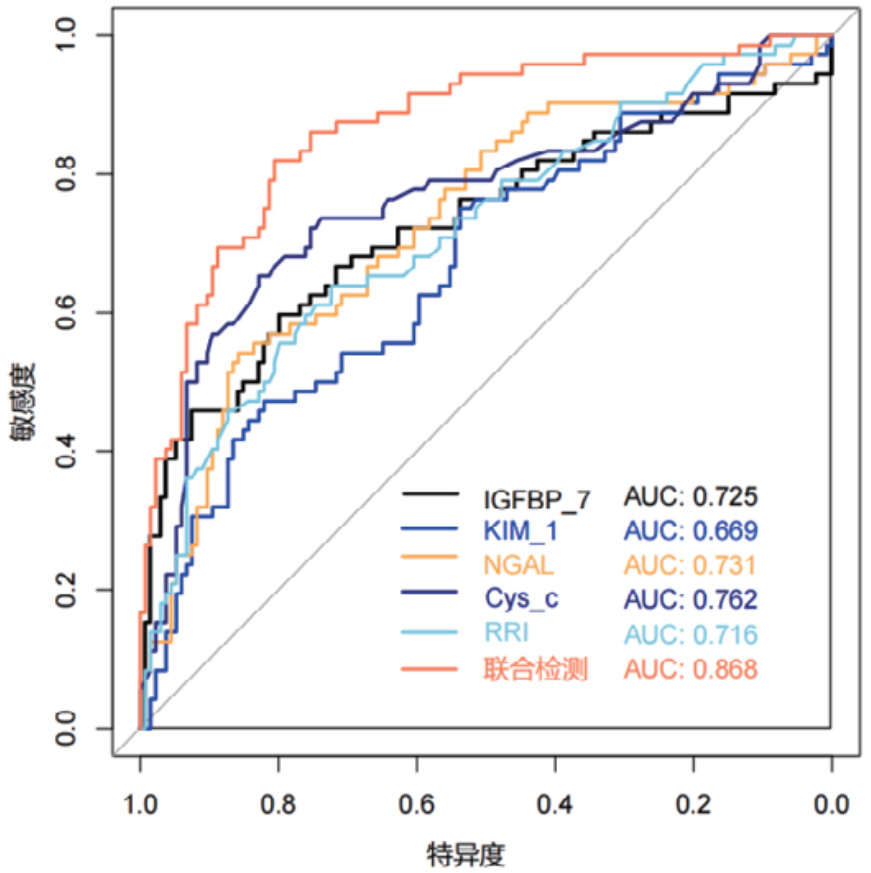

对各时间段血清Cys-C、IGFBP-7、KIM-1、NGAL和超声RRI水平及联合检测进行ROC曲线绘制,计算不同时间段联合检测的AUC值、最佳截断值、敏感度、特异度和约登指数。结果显示,联合检测0 h、12 h、24 h和48 h的AUC值分别为0.838(95%CI: 0.778~0.897)、0.852(95%CI: 0.797~0.907)、0.868(95%CI: 0.816~0.921)和0.872(95%CI: 0.820~0.924),见表 3。不同时段的AUC值提示联合检测的诊断效能要高于单项指标检测,结果见图 2、图 3、图 4和图 5。各指标各时间段的详细回归系数、标准误、P值、比值比(OR)及其95%置信区间见补充表S1。

| 检测变量 | AUC | 95%CI | 截断值 | 敏感度 | 特异度 | 约登指数 |

| 联合检测(0 h) | 0.838 | 0.778~0.897 | 0.403 | 69.44% | 82.83% | 0.523 |

| 联合检测(12 h) | 0.852 | 0.797~0.907 | 0.316 | 79.17% | 79.10% | 0.583 |

| 联合检测(24 h) | 0.868 | 0.816~0.921 | 0.309 | 81.94% | 80.60% | 0.625 |

| 联合检测(48 h) | 0.872 | 0.820~0.924 | 0.272 | 84.72% | 78.36% | 0.631 |

| 图 4 单项和联合检测24 h的ROC曲线 |

|

|

|

本研究结果显示,既往存在肾脏疾病是发生AKI的危险因素,AKI患者早期SCr和BUN水平显著高于非AKI组患者,AKI组患者的eGFR指标更低。其次,AKI组患者在0 h、12 h、24 h和48 h时间段内,血清NGAL、Cys-C、KIM-1、IGFBP-7水平及超声RRI值均高于非AKI组更高。这一结果提示,该生物标志物和RRI值的变化可以作为AKI早期诊断的敏感指标。此外,RRI值的升高也反映了肾脏血管阻力的增加和肾脏血流灌注的减少,是AKI发生的重要预测因素。但是单一指标的检测存在局限性,各项指标绘制的ROC曲线AUC值相对偏低,联合检测的AUC值优于各单项指标检测,其中联合检测48 h的AUC值最高为0.872(95%CI: 0.820~0.924),且敏感度和特异度相对较高。对各时间段联合检测指标显示各时间段预测性能比较接近,AUC值均大于0.8,提示联合检测稳定性和预测性能良好。此外,对各指标随时间变化的动态监测显示,Cys-C和KIM-1呈持续上升趋势,IGFBP-7在12 h达峰值后略有下降,NGAL在早期即显著升高并维持高水平,RRI随时间推移逐渐上升。这些指标的动态监测为AKI的早期识别、严重程度评估和预后判断提供了重要依据。不同指标在时间维度上的变化特征也反映了AKI发生发展过程中不同的病理生理机制。